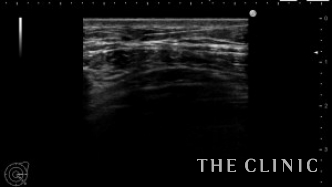

エコーでは大きなしこり以外にも小さなしこりを多数認めました。

除去後ヒアルロン酸は消失しました。

ヒアルロン酸注入によるしこりのエコー診断カルテ